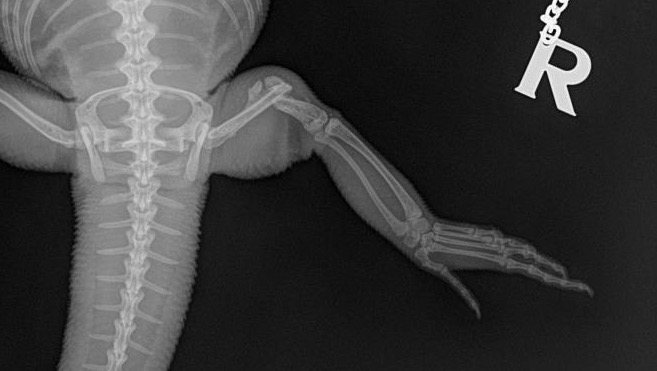

After 3 months of her leg being on a splint we brought her back to the vet. The Vet did an X-ray and gave us good news that the splint was ready to be removed, since a soft callus has formed where the break was. Unfortunately this was the wrong decision, for the moment we brought her home her leg seemed to have broken again, so we brought her back to the vet. And in this visit the vet had informed us that her leg and the soft callus that formed broke. The only way at this point to have Groot walk normally again is to do a major surgery on her broken leg.

This is her last xray when we found out her leg wasnt still moving after the splint removed.